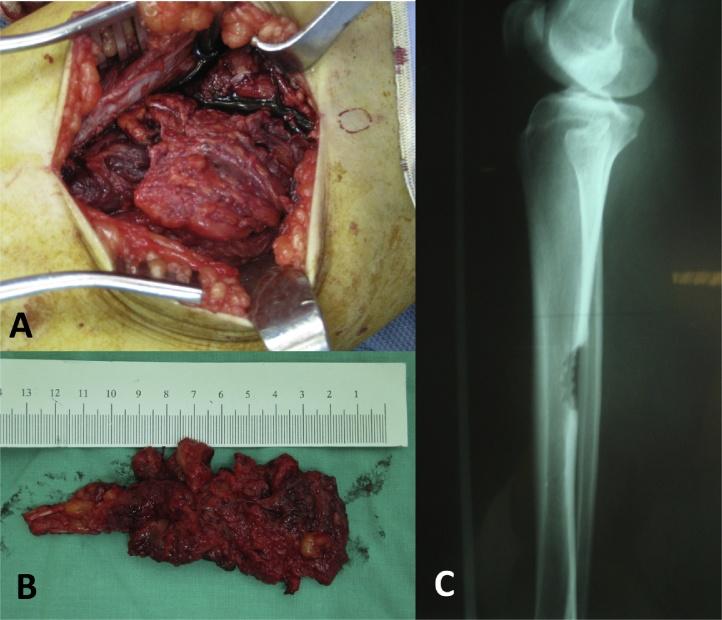

PRESENTATION OF CASE

We present a case of forty-one-year-old female diagnosed with intramuscular hemangioma, mimicking osteoid osteoma, adjacent to the periosteal region of tibia diaphysis treated by surgical excision.

When intramuscular hemangioma occurs nearby a bone structure, it can cause cortical, medullary and periosteal bone changes that are frequently misdiagnosed by plain radiography. Due to their infrequency, deep location, and atypical presentation, these lesions are seldom diagnosed at presentation. The hemangioma of the periosteal region can be locally destructive due to compression exerted on neighboring structures. It does not regress spontaneously, and surgical excision is frequently needed.

Intramuscular hemangioma of periosteal region occurs most commonly adjacent to long bones of the lower limb. They can cause hypertrophic periosteal reactions mimicking a periosteal or parosteal tumor. Although osteoid osteoma was considered in the differential diagnosis, MRI with enhancement should be performed to exclude intramuscular hemangioma. This may avoid unnecessary aggressive en-bloc tumor excisions resulting in bone weakness and prolonged rehabilitation. This case report has been written in line with the SCARE criteria (Agha et al., 2016 [1]).